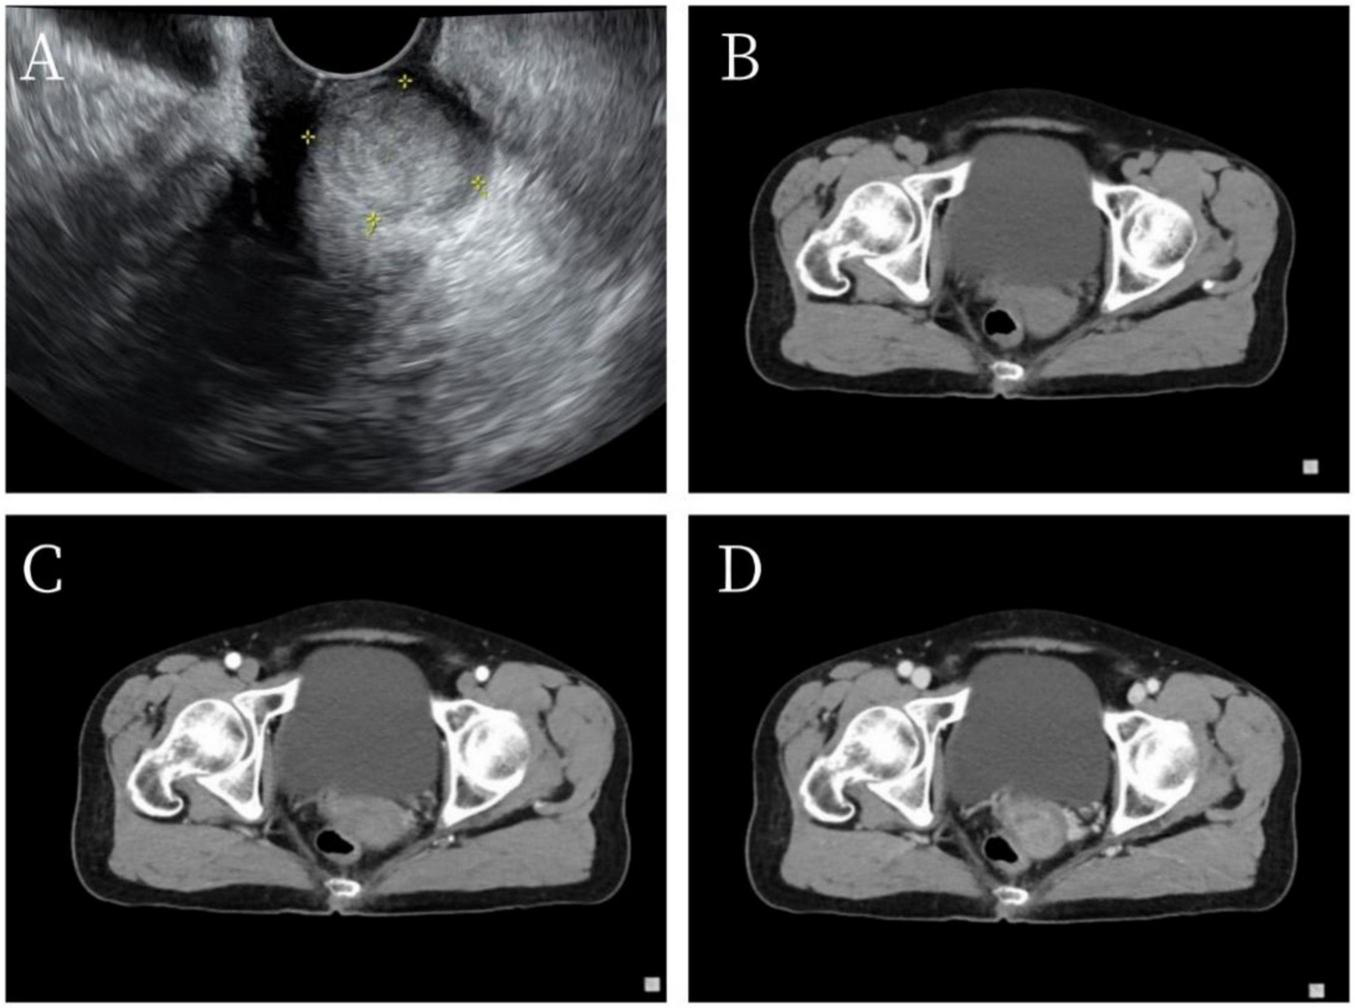

A 69-year-old female patient was admitted to our hospital on June 14, 2023, for surgical treatment of vaginal bleeding that had persisted for more than a year. Initially, the patient experienced minor post-coital vaginal bleeding without associated abdominal pain or hematuria, along with occasional yellowish discharge. Polymerase chain reaction was used to detect 21 HPV genotypes in cervical secretion specimens. High-risk HPV genotyping was positive for HPV types 16, 58, and 42. Transvaginal ultrasonography revealed a 24 × 19-mm hypoechoic nodule in the posterior lip of the cervix, with clear boundaries and uneven internal echoes. This suggested the presence of a cervical leiomyoma (Figure 1A). Contrast-enhanced pelvic computed tomography indicated a slightly enlarged cervix with uniform enhancement and no abnormal density in the adnexal regions. Imaging confirmed slight cervical enlargement with enhancement (Figures 1B–D). The patient had no chronic diseases; no history of surgery, trauma, infectious diseases, or allergies; and did not smoke or drink.

FIGURE 1

Imaging findings. (A) Vaginal ultrasonography indicated a 24 × 19-mm hypoechoic nodule in the posterior lip of the cervix with clear boundaries and heterogeneous internal echoes. (B–D) Pelvic computed tomography revealed thickening of the cervical region with persistent enhancement on early- and late-phase scans after contrast administration.